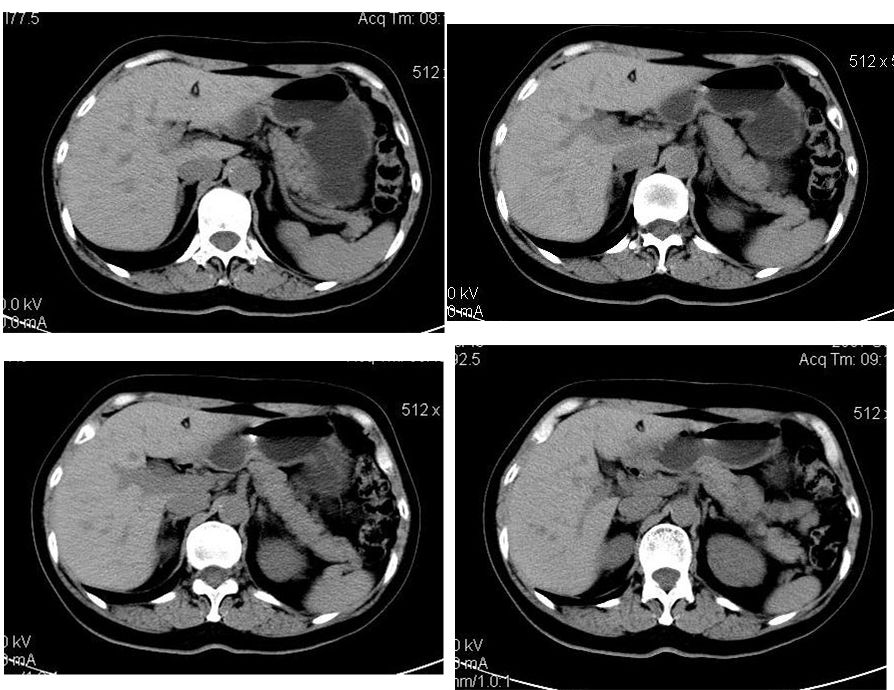

该患者去年9月份在我院ct检查,今年随访,患者家属介绍说上海中山医院做了一个什么检查考虑良性占位,后手术病理是血管平滑肌脂肪瘤。

学习了,这可能是脂肪含量少的血管平滑肌脂肪瘤,因血管丰富所以动脉期密度升高明显,但该患无肝硬化表现,所以,诊断肝癌,依据不足.谢谢上传.对今后工作是一个提醒.

该病例给我们影像医生上了一课,影像上的特征相对性更强。今后工作中吸取教训,避免出现闭门造车的情况,多结合临床的重要性。再次表示感谢